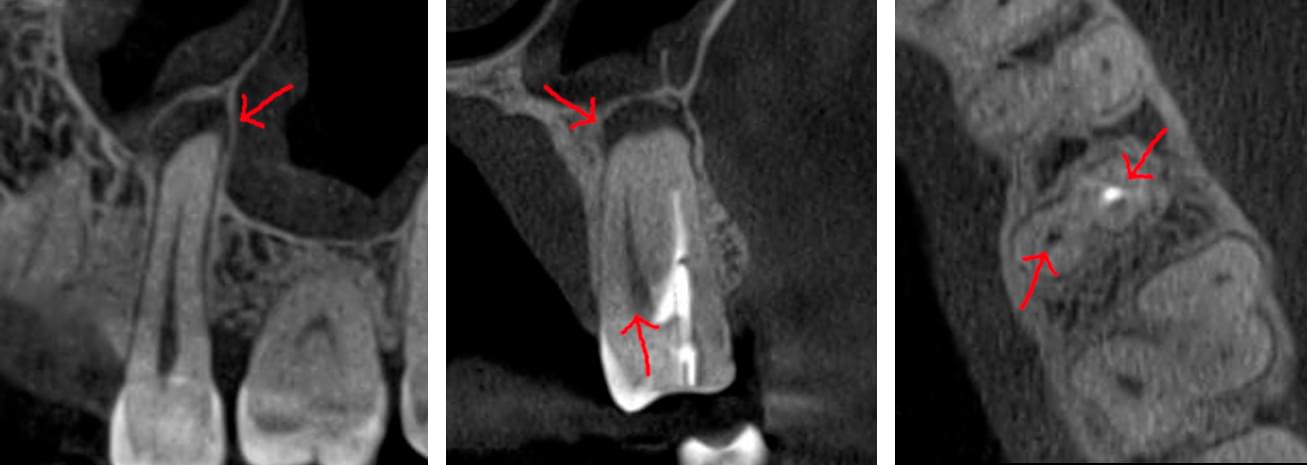

Коли коріння «ховає сюрпризи» - Корені зубів часто мають складну кривизну, гачкоподібні закручення або розгалуження, які на звичайному 2D-знімку накладаються один на одного, створюючи ілюзію прямого каналу. На плоскій картинці неможливо побачити реальний об'єм та напрямок вигину, що критично важливо при видаленні «зубів мудрості» або ендодонтичному лікуванні. КТ MyRay дає змогу лікарю заздалегідь побачити 3D-геометрію кожного кореня, оцінити його близькість до нижньощелепного нерва чи гайморової пазухи та підібрати правильну тактику роботи. Це мінімізує ризики поломки інструменту в каналі або травмування сусідніх структур, перетворюючи складну хірургію на прогнозовану процедуру.